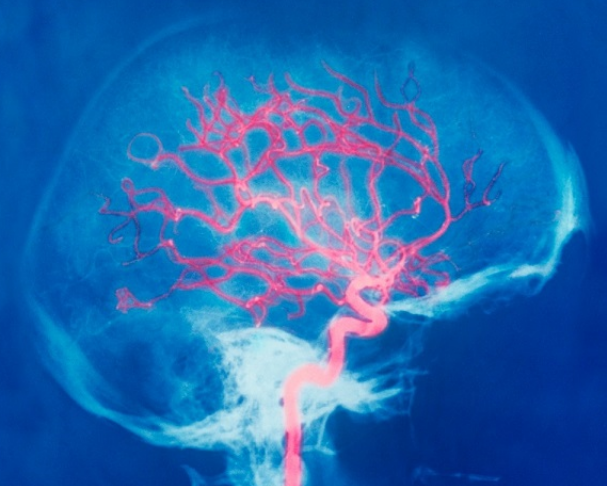

뇌에 있는 혈관이 막히면서 주변의 세포들이 괴사하는 질병인 뇌경색은 노화가 진행될 수록 발병률이 높은 질환입니다. 초기에 치료하지 못할 경우 장애가 생겨 정상적인 활동이 불가능해지기 때문에 뇌경색 초기증상을 체크하는 것은 매우 중요합니다. 동맥경화나 심장병, 혈관박리 등에 의해 주로 나타나며, 당뇨병이나 고혈압, 고지혈증이 있다면 이 글을 꼼꼼하게 읽어주시기 바랍니다.